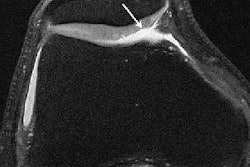

"We were looking at T1 and T2 scores as a potential secondary marker for enthesopathy, which is irregularity of the surface of the greater tuberosity that can be found on MRI. We found that a greater severity of enthesopathy was predictive of rotator cuff tear on both T1-weighted and T2-weighted images," said Dr. Adam Ross Coen from the New York University School of Medicine in New York City.

The two radiologists examined coronal oblique T1-weighted and T2-weighted fat-suppressed images, grading them on a scale of 1 (indicating no enthesopathy) to 5 (worst enthesopathy). Investigators then utilized a logistic regression model to evaluate the significance of T1 and T2 scores in diagnosing rotator cuff tears and impingement.

In the statistical analysis, Coen and his team found that T1 and T2 enthesopathy scores served as independent significant predictors of cuff tears. In addition, scores of 4 or 5 were highly specific for tears, with specificities of 93% for both T1 and T2 images. The T1 and T2 scores were also independent significant predictors of impingement with and without age and gender adjustment, the investigators noted.